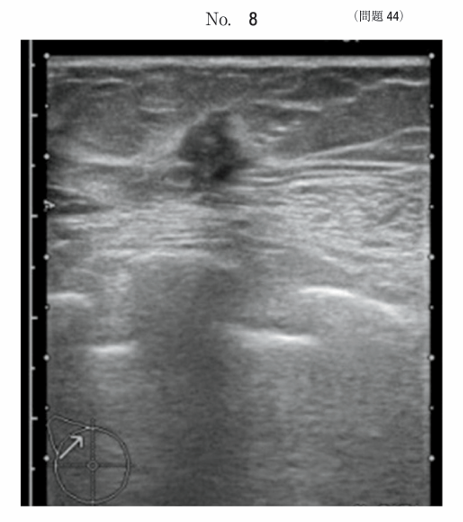

午前/問題44

乳腺結節の超音波画像別冊No. 8を別に示す。所見で正しいのはどれか。2つ選べ。

1.辺縁不整

2.境界明瞭

3.囊胞性病変

4.粗大石灰化病変

5.縦横比D/W > 1